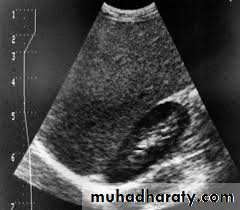

Renal ultrasound is a simple noninvasive examination .The kidney is bean shaped and has bright central echoes because of the fat surrounding the collecting system.

Normal renal ultrasound.

A longitudinal view of the right kidney was obtained by passing the sound beam through the right lobe of the liver. The kidney is seen behind this, outlined by the markers. The central bright echoes in the kidney are due to fat around the collecting system.